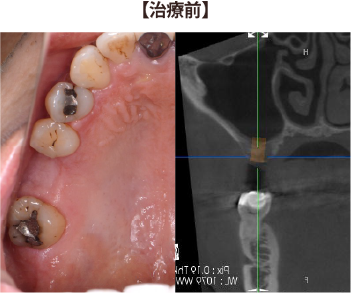

②左上の奥歯2本が無く、インプラントを入れるための骨がほとんど無い症例

左上の歯が無くなった部分に骨の高さが無く、このままではインプラントが骨からはみ出てしまう。

上顎洞底挙上術と人工骨を足す手術を併用し、1回の手術でインプラントを埋入できました。

2ヶ月半ほど骨との結合を待った後に、かぶせ物を製作しています。

埋入から1年後も安定し、骨の高さも維持しています。

全く不安や問題なく、自分の歯のように噛めています。

| 治療期間 : | 3ヶ月 |

| メリット : | ブリッジや入れ歯に比べて、両隣の歯を削ること無く、強い歯を再建することができる。 入れ歯やブリッジに比べて自然なかみ合わせを得られる。 概して入れ歯やブリッジより長持ちし、他の残存歯における負担も減らすことで、残存歯本来の寿命を全うできることが多い。 虫歯にならない。 |

| リスク・副作用 : | 手術が必要であり、感染のリスクを伴う。 術後に一時的に腫れたり痛みが出ることがある。 治療完了までに数か月の期間を要する。 自費治療であり、保険治療より高額である。 |

| 費用(自費治療分): | 合計金額 ¥1,023,000(税込) (ソケットリフト法×2、人工骨使用、SLActive加算×2、ジルコニア冠の場合) |